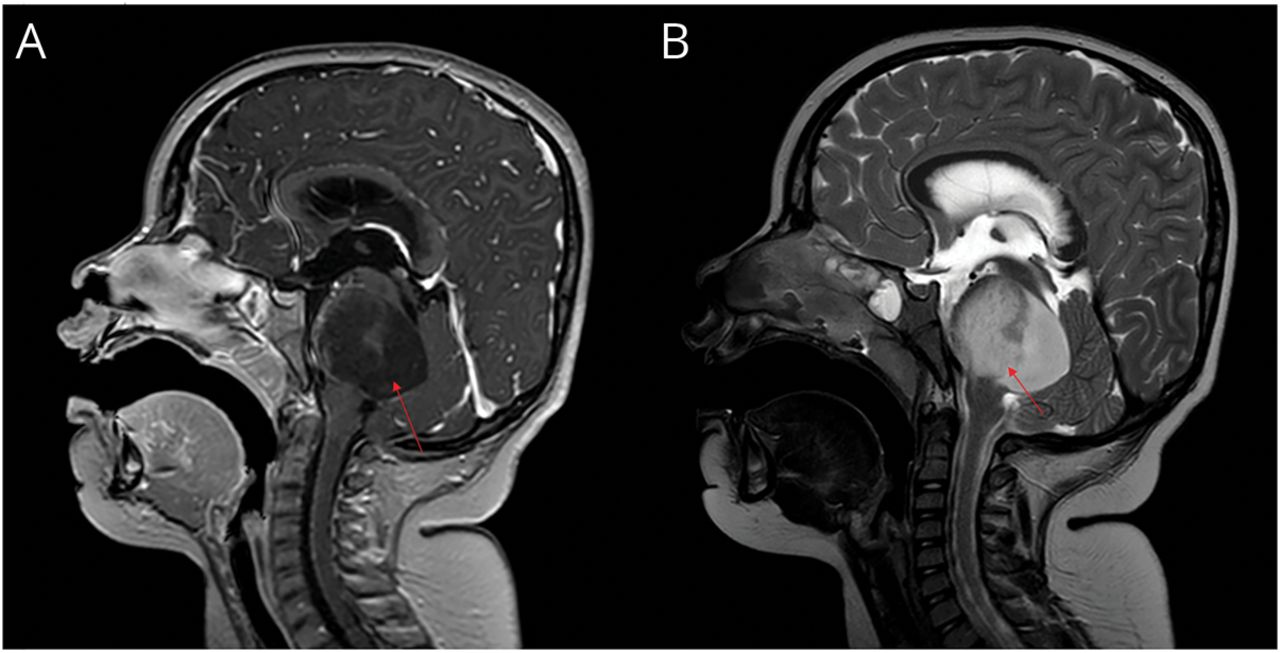

大脑的磁共振t1加权图像(矢状视图)显示质量集中在脑桥(箭头)和显著的扩张和温和的扩展中脑以及消灭第四脑室后外生型的组件导致早期脑积水(a) t2加权图像显示高信号强度的肿瘤(B)。